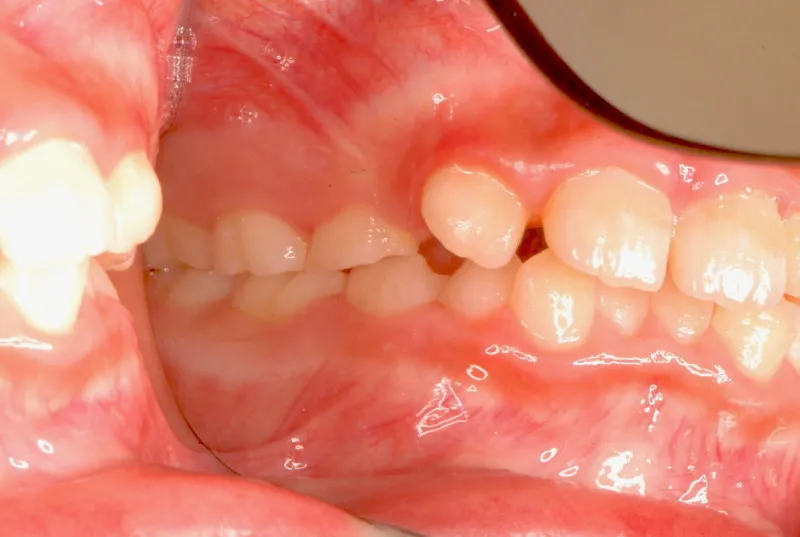

初診時年齢 小学校3年生 (男性) 主訴 前歯がゆがんでいる・ガタガタ

診断名 叢生・交叉咬合 装置名

上下の幅が狭くガタガタに生えています。